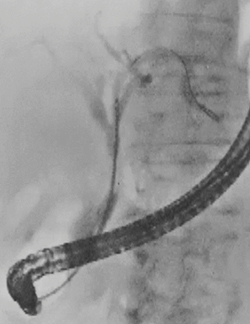

●症例1:IgG4-SC(70歳代、男性)(図2)

本症例は、IgG4値は37.1mg/dLの正常値であり、IDUSでは表面に若干凹凸が見られ、良悪性の鑑別は困難であった。生検の結果、病理学的な悪性所見はなく、IgG4の免疫染色も陰性であった。しかし、狭窄が強いにもかかわらず黄疸がほとんど見られなかったため、ステロイド治療を行った結果、1か月後に改善した。

図2 症例1:IgG4-SC(70歳代、男性)